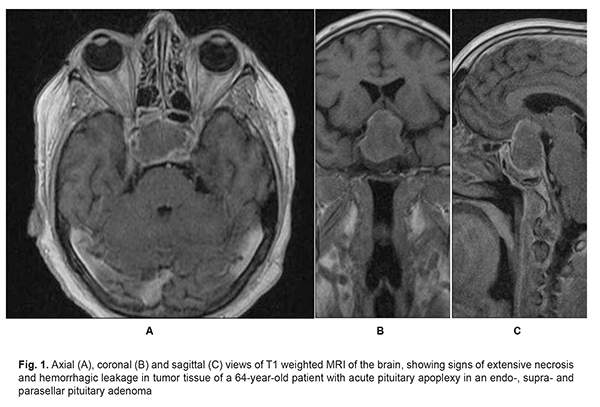

Introduction Pituitary apoplexy is a clinical condition characterized by sudden headache, nausea, vomiting, impaired consciousness, visual and oculomotor disturbances, and meningeal symptoms resulting from impaired circulation in pituitary adenoma. Changes in tumor tissue such as necrosis, hemorrhagic leakage, hemorrhage, formation of hematomas and intratumoral hemorrhagic cysts result in a rapid increase in tumor volume and changes in tumor relationships with adjacent brain structures [1- 3] (Fig. 1).